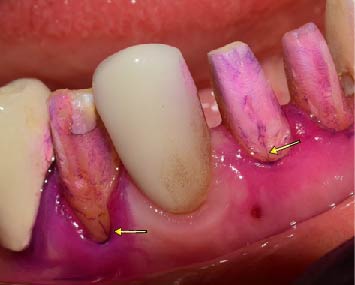

Las manifestaciones clínicas del síndrome de diente fisurado pueden variar desde sensibilidad dental hasta fracturas completas del diente. Los pacientes pueden experimentar dolor intermitente al masticar, sensibilidad al frío o al calor, así como una sensación de molestia al morder. La dificultad en el diagnóstico radica en la naturaleza asintomática de la fisura, lo que destaca la importancia de una evaluación clínica minuciosa.

Diagnóstico y tratamiento: Identificar con precisión el síndrome del diente fisurado puede involucrar pruebas como radiografías, examen clínico y evaluación táctil con herramientas dentales específicas. El tratamiento odontológico varía dependiendo de la severidad de la fisura, se debe definir correctamente la ubicación, profundidad y extensión de la grieta para seleccionar y realizar un protocolo restaurativo adecuado. De este modo, mediante un tratamiento restaurador eficaz, se puede limitar la propagación de la fractura y la posible enfermedad pulpar asociada. Abarcando desde restauraciones simples, incrustaciones hasta tratamientos de conducto o incluso extracción en situaciones más críticas donde la fisura llega hasta la raíz dentaria.